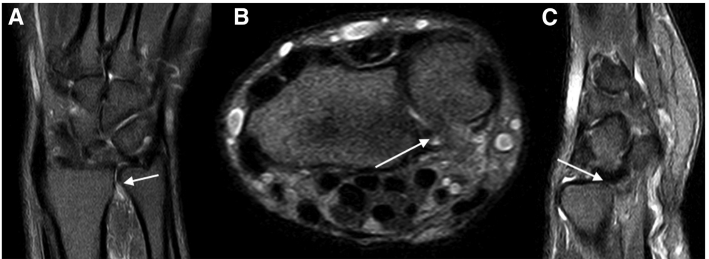

Chụp MRI không tiêm thuốc tương phản giúp chẩn đoán chính xác loại rách, vị trí mảnh rách, và mức độ lệch/lật của mảnh rách đó (Hình 2).

Suzuki và cộng sự¹, trong loạt ca lâm sàng gồm 24 trường hợp, đã phân loại cơ chế bệnh sinh của hiện tượng kẹt khi xoay ngửa dựa trên vị trí mảnh rách và hướng lệch của mảnh vạt. Cụ thể, mảnh rách bị lệch về phía gan tay sẽ chắn đường trượt ra trước (volar subluxation) của đầu xương trụ, dẫn đến hiện tượng kẹt ở cuối tầm xoay ngửa. Tuy nhiên, không có trường hợp nào trong loạt nghiên cứu này hay các tài liệu khác ghi nhận hạn chế xoay sấp cẳng tay, điều này cho thấy vẫn còn khoảng trống trong hiểu biết về các mảnh rách dạng vạt và cơ chế gây triệu chứng. MRI không cản quang là công cụ hữu ích để xác nhận sự tồn tại của rách dạng vạt và vị trí lệch của mảnh rách.

Theumann và cộng sự⁵ đã ghi nhận một trường hợp rách thành phần ngoại vi xa của TFCC, trong đó mảnh rách bị gập lại vào chính nó, tạo hình ảnh “kính râm” (sunglass appearance) trên MRI. Kể từ đó, nhiều kiểu lệch mảnh rách đã được ghi nhận, như trong loạt ca của Jose và cộng sự⁷, trong đó một mảnh rách bị lệch vào ngách trước mỏm trâm (prestyloid recess) và một mảnh khác lệch vào khớp quay–trụ xa (DRUJ) — tương tự như trong trường hợp của chúng tôi.